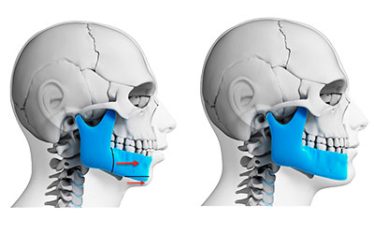

Existem pessoas que precisam fazer cirurgias, tais como: Ortognática, ATM, remoção de Tumores faciais e bucais, Estética (próteses faciais sob medida), Sisos complexos ou Sisos de pacientes com problemas de saúde e NÃO POSSUEM CONVÊNIO MÉDICO.

Temos uma solução acessível para esse público de pessoas, onde o paciente terá um valor fechado para cada procedimento citado, incluindo: Hospital com Qualidade + Materiais Utilizados + Instrumentador + Honorário Médico e detalhe, sem precisar aguardar liberações de convênio e muitas vezes gastos com ação judicial para liberação da cirurgia.

Nessa modalidade de atendimento, que chamamos de BMF sem convênio